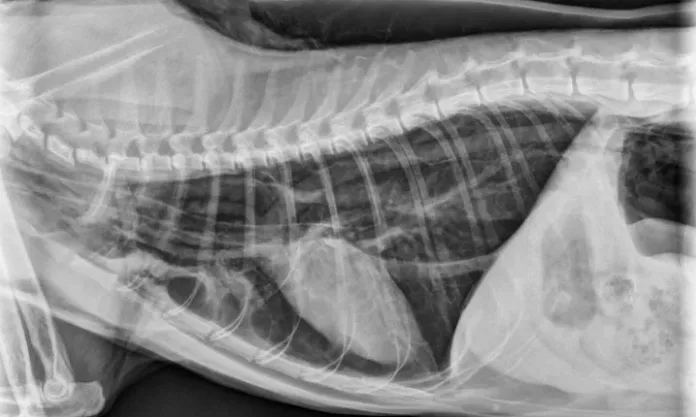

In this diagram, the trachea is denoted by dotted lines and the endotracheal tube and ETTC by solid lines. The high-volume, low-pressure cuff (left) exerts minimum pressure on the tracheal mucosa, whereas the high-pressure, low-volume cuff (right) can cause excessive pressure on the tracheal mucosa.

All patients, particularly cats, should be carefully intubated using high-volume, low-pressure cuffed tubes, which are less likely to create excess pressure (Figure).